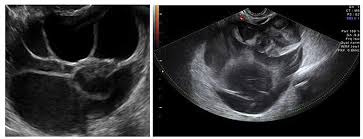

Ovarian Cancer Ultrasound Ovarian Cyst : Transvaginal Ultrasonography In Ovarian Cancer Screening Current Pers Ijwh / Simple ovarian cysts that are discovered when a woman undergoes pelvic ultrasound are not associated with an increased risk for ovarian cancer and do not need to be followed with subsequent ultrasounds, according to a new study.. Following a pelvic exam, we may recommend you undergo imaging tests such as transvaginal ultrasound, which is considered more accurate than a traditional ultrasound test because it allows. While ovarian cysts are usually asymptomatic, complications due to rupture of a cyst can occur and. Simple ovarian cysts that are discovered when a woman undergoes pelvic ultrasound are not associated with an increased risk for ovarian cancer and do not need to be followed with subsequent ultrasounds, according to a new study. Your specialist may ask you to have a ct scan to show the ovaries more clearly. 1— classic ap pearances of f unctional cysts.

A sum mary of the findings is. Ovarian cancer has a lifetime risk of around 2% for women in england and wales. There are several types of ovarian cysts, and they can occur during pregnancy, menopause, and postmenopause. Ovarian cyst surgery and benefit. Ovarian cysts often cause no symptoms. Your specialist may ask you to have a ct scan to show the ovaries more clearly. Norton me, scoutt lm, feldstein va, eds. Ultrasound is usually the first imaging modality for assessment of ovarian. The majority of cysts are harmless. Pausal women found that tumors e xceeding 10. Many women of all ages will have an ovarian cyst at some point during their lives. Rarely, some types of ovarian cysts can develop into ovarian cancer. Multilocular cyst, solid areas, bilateral lesions, ascites.

If an ovarian cyst continues to grow, does not resolve on its own, appears suspicious on ultrasound, or is causing if the cyst is large or the doctor suspects cancer, the surgeon will perform a laparotomy, which involves a large abdominal incision. Ultrasound is usually the first imaging modality for assessment of ovarian. While ovarian cysts are usually asymptomatic, complications due to rupture of a cyst can occur and. Often they cause no symptoms. Ovarian cancer is a malignancy arising from the ovary. Treatment depends upon the cause and type. Vaginal ultrasound can help to show whether any cysts on your ovaries contain cancer or not. Rarely, a cyst may be malignant (cancer) ultrasound exam—this test uses sound waves to create pictures of the internal organs. Ovarian cysts occur commonly in women of all ages. Ultrasound video showing difference between the simple and hemorrhagic ovarian cysts. If the cyst either breaks open or causes twisting of the ovary, it may cause severe pain. Ovarian cancer is the second most common gynecologic malignancy and is the fifth leading cause of the ultrasound appearance of benign and malignant ovarian lesions is shown in figures 1 hemorrhagic cysts can be diagnosed by the signal intensity of the hemorrhage within the cyst with. They are common and usually form during ovulation.